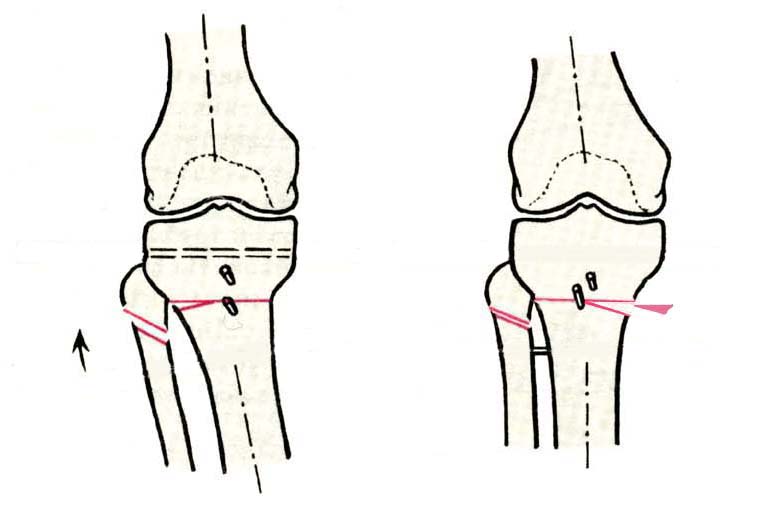

Дополнительными методами диагностики являлось измерение внутрикостного давления в зоне гипернагрузки и радионуклидные исследования нуклидами технеция. Применялись различные варианты остеотомий на различных сегментах. Для коррекции варусной-торсионной деформации:

высокие плюс, минус остеотомии большеберцовой кости,косая остеотомия малоберцовой. Для коррекции вальгусной деформации применялась плюс, минус надмыщелковая остеотомия бедренной кости. Фиксацию при высокой подмыщелковой остеотомии производили уникальной клинковой пластиной и тяговыми кортикальными винтами. Угол коррекции выставлялся

специальным угломером и направителем.

В зависимости от баланса связок, комбинировали (+-)остеотомии или производили полную

минус или плюс остеотомию